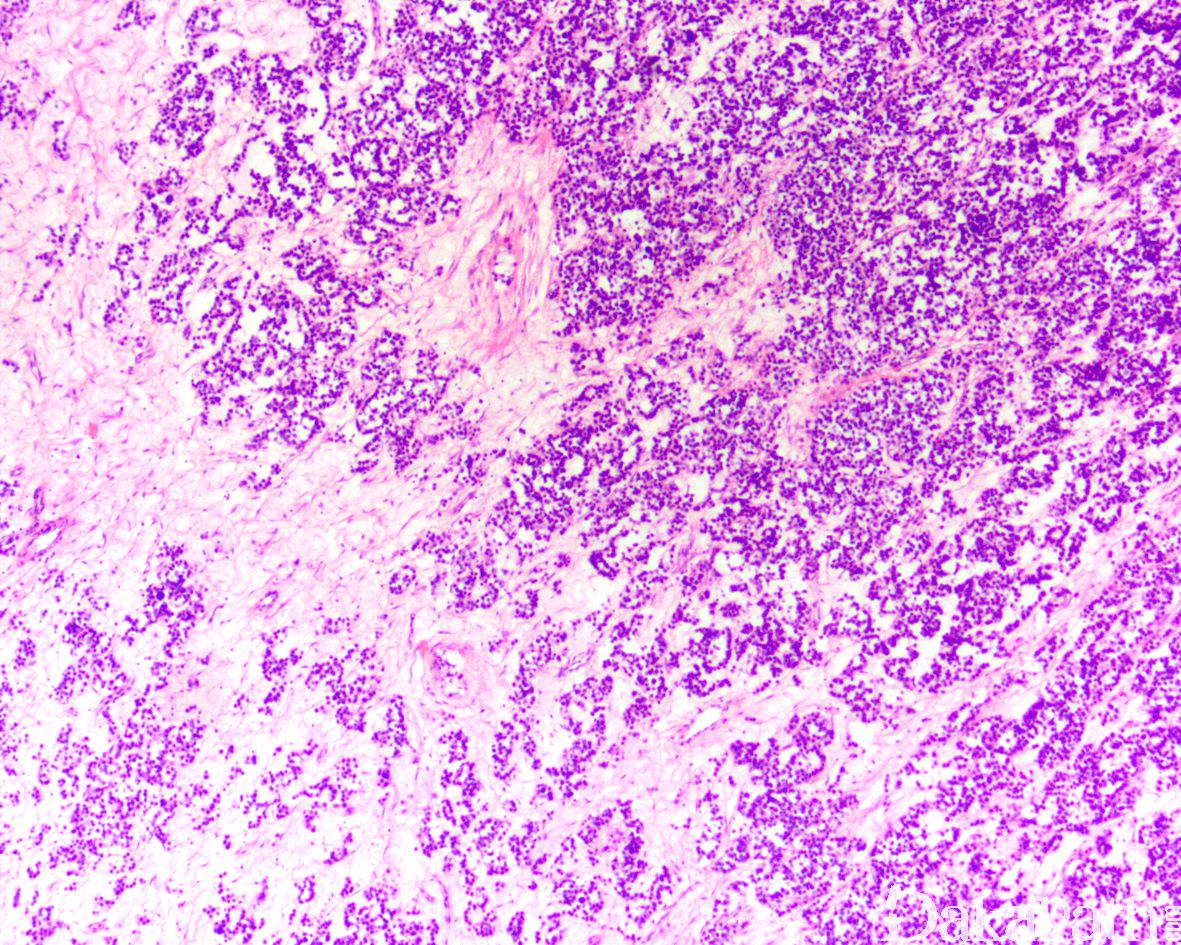

肿瘤细胞弥漫或多结节状增生,可穿插明显的无细胞水肿区,有时结界内的圆形实体细胞巢中央水肿液聚集,形成假滤泡样结构,部分肿瘤细胞可呈现粗梁状和 巢状结构伴有周围细胞的栅栏状排列,类似于类癌;

结节周围可见纤维素样蛋白物质围绕;

标志性形态学特征是肿瘤细胞的多态性,常出现 3 种细胞(比例多少不等):

1)小细胞:细胞核形态一致,圆形,深染,胞质少,类似于淋巴细胞大小;

2)中等大细胞:核小,圆形,染色质细颗粒状或细丝状,可见小核,大小不一,胞浆嗜酸性或双色性,部分病例胞质淡染;

3)巨细胞:体积大,具一个或多个细胞核,可见巨核细胞以及绳索样染色质结构;

胞膜通常不清楚,核分裂像及非典型核分裂像通常较多,可见大量凋亡细胞;

间质稀少,罕见类似于精原细胞瘤的纤细的纤维性分隔;

偶见淋巴细胞浸润,通常位于结节周围;罕见肉芽肿反应;